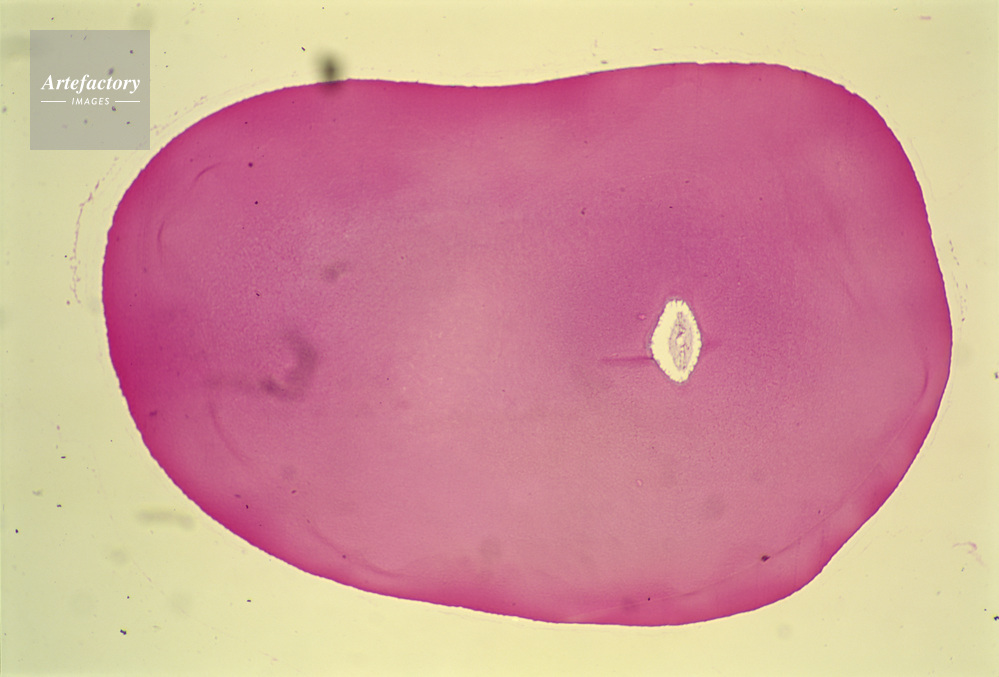

| 作品タイトル | 顕微鏡写真 | モデルリリース | なし | |

| キャプション | 歯,人間 | 制限事項 | ||